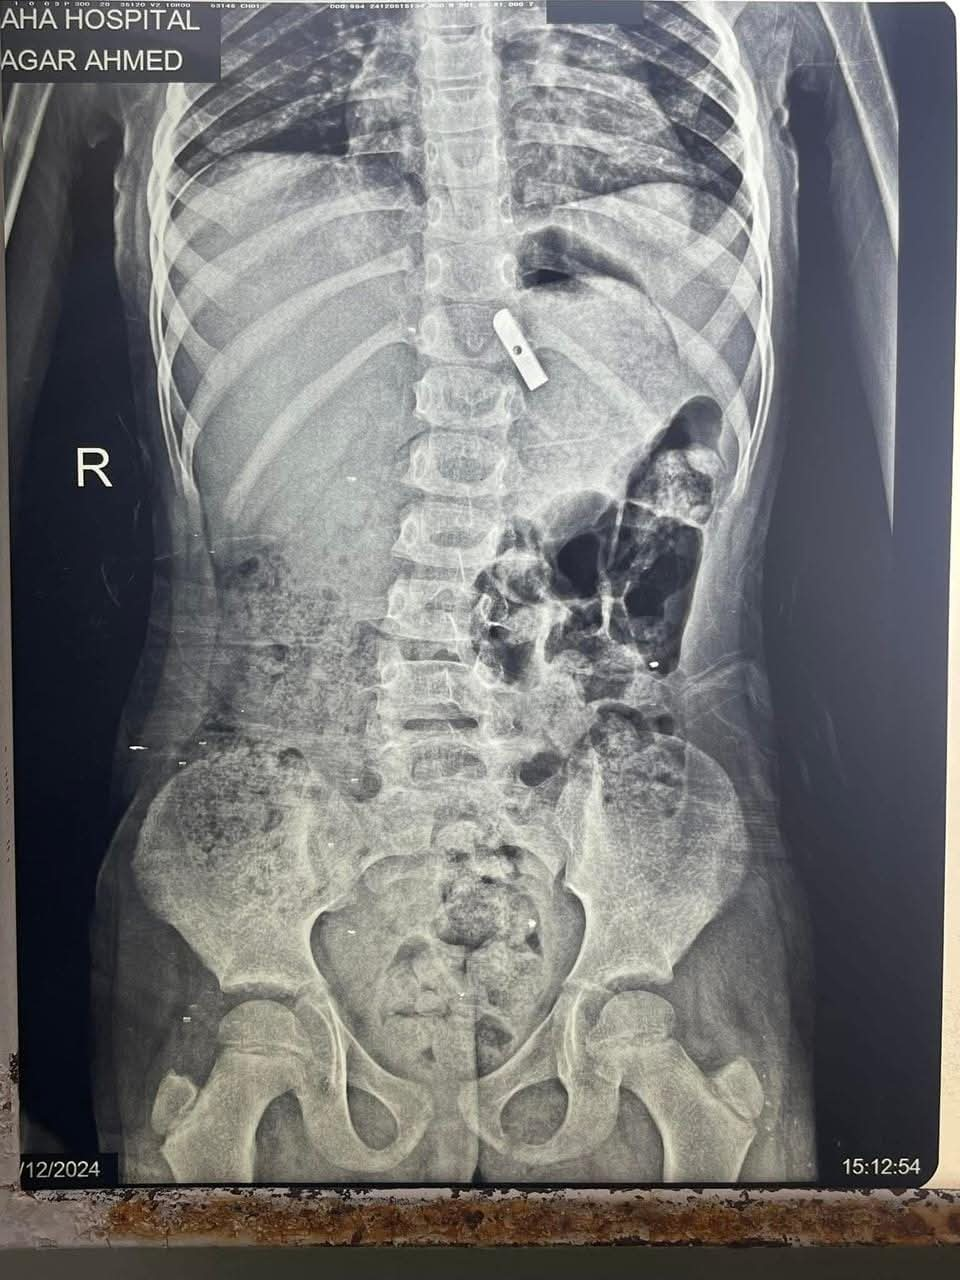

وتابعت المستشفي، أنه تم حجز الحالة بالمستشفى وتم عمل اللازم من إشاعات وتحاليل، وتم تشخيص الحالة بوجود جسم غريب داخل المعدة، وعلى الفور تم دخول الطفلة إلى غرفه العمليات، وتم استخراج قطعة معدنية حادة من براية القلم الرصاص، من جدار المعدة باستخدام منظار الجهاز الهضمى.

الأشعة